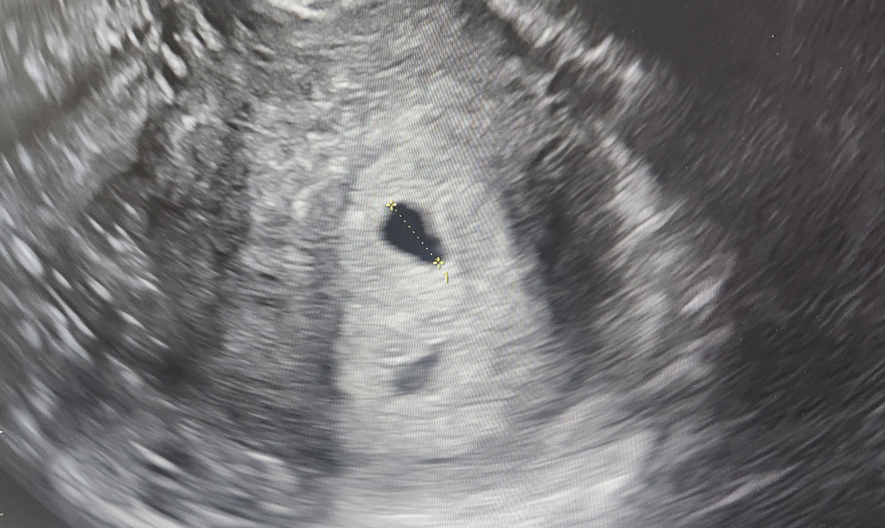

6주차는 난황이 보여야 하는 중요한 시기였는데, 초음파 검사 결과 아기집만 보였고 난황은 보이지 않았습니다.

아기집 크기도 7.6mm로 주수보다 작았습니다.

선생님께서는 아기집 크기가 여전히 작으며, 이번 주에는 난황이 꼭 보여야 하는데 보이지 않는다고 설명해주셨습니다.

이번 초음파에서는 아기집 크기가 9.4mm로 약간 자란 모습이었지만, 난황은 여전히 보이지 않았습니다.